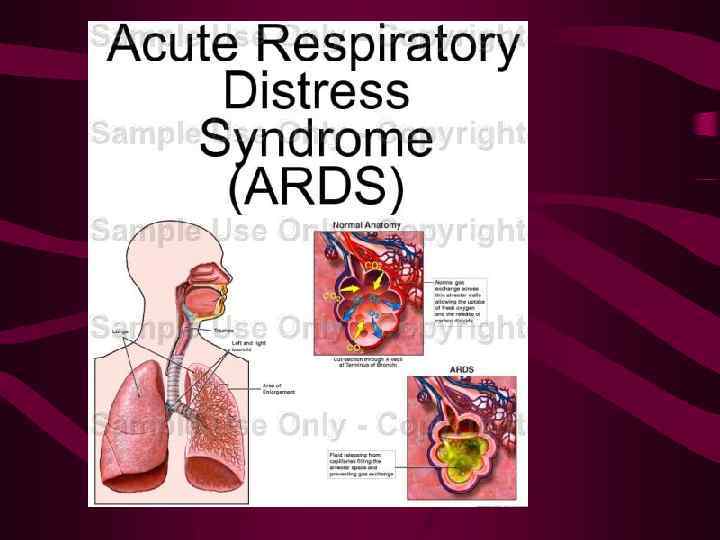

Отеки при повреждении капилляров Синдром острого повреждения легких (СОПЛ), респираторный дистресс синдромом взрослых (РДСВ), синдром шокового легкого (СШК), синдром влажных легких, некардиогенный отек легких и т. д.

Отеки при повреждении капилляров Синдром острого повреждения легких (СОПЛ), респираторный дистресс синдромом взрослых (РДСВ), синдром шокового легкого (СШК), синдром влажных легких, некардиогенный отек легких и т. д.

Отеки при повреждении капилляров Повреждение стенок легочных капилляров, прежде всего их базальной мембраны возникает при эндогенных и экзогенных воздействиях на микроциркуляторное русло.

Отеки при повреждении капилляров Повреждение стенок легочных капилляров, прежде всего их базальной мембраны возникает при эндогенных и экзогенных воздействиях на микроциркуляторное русло.